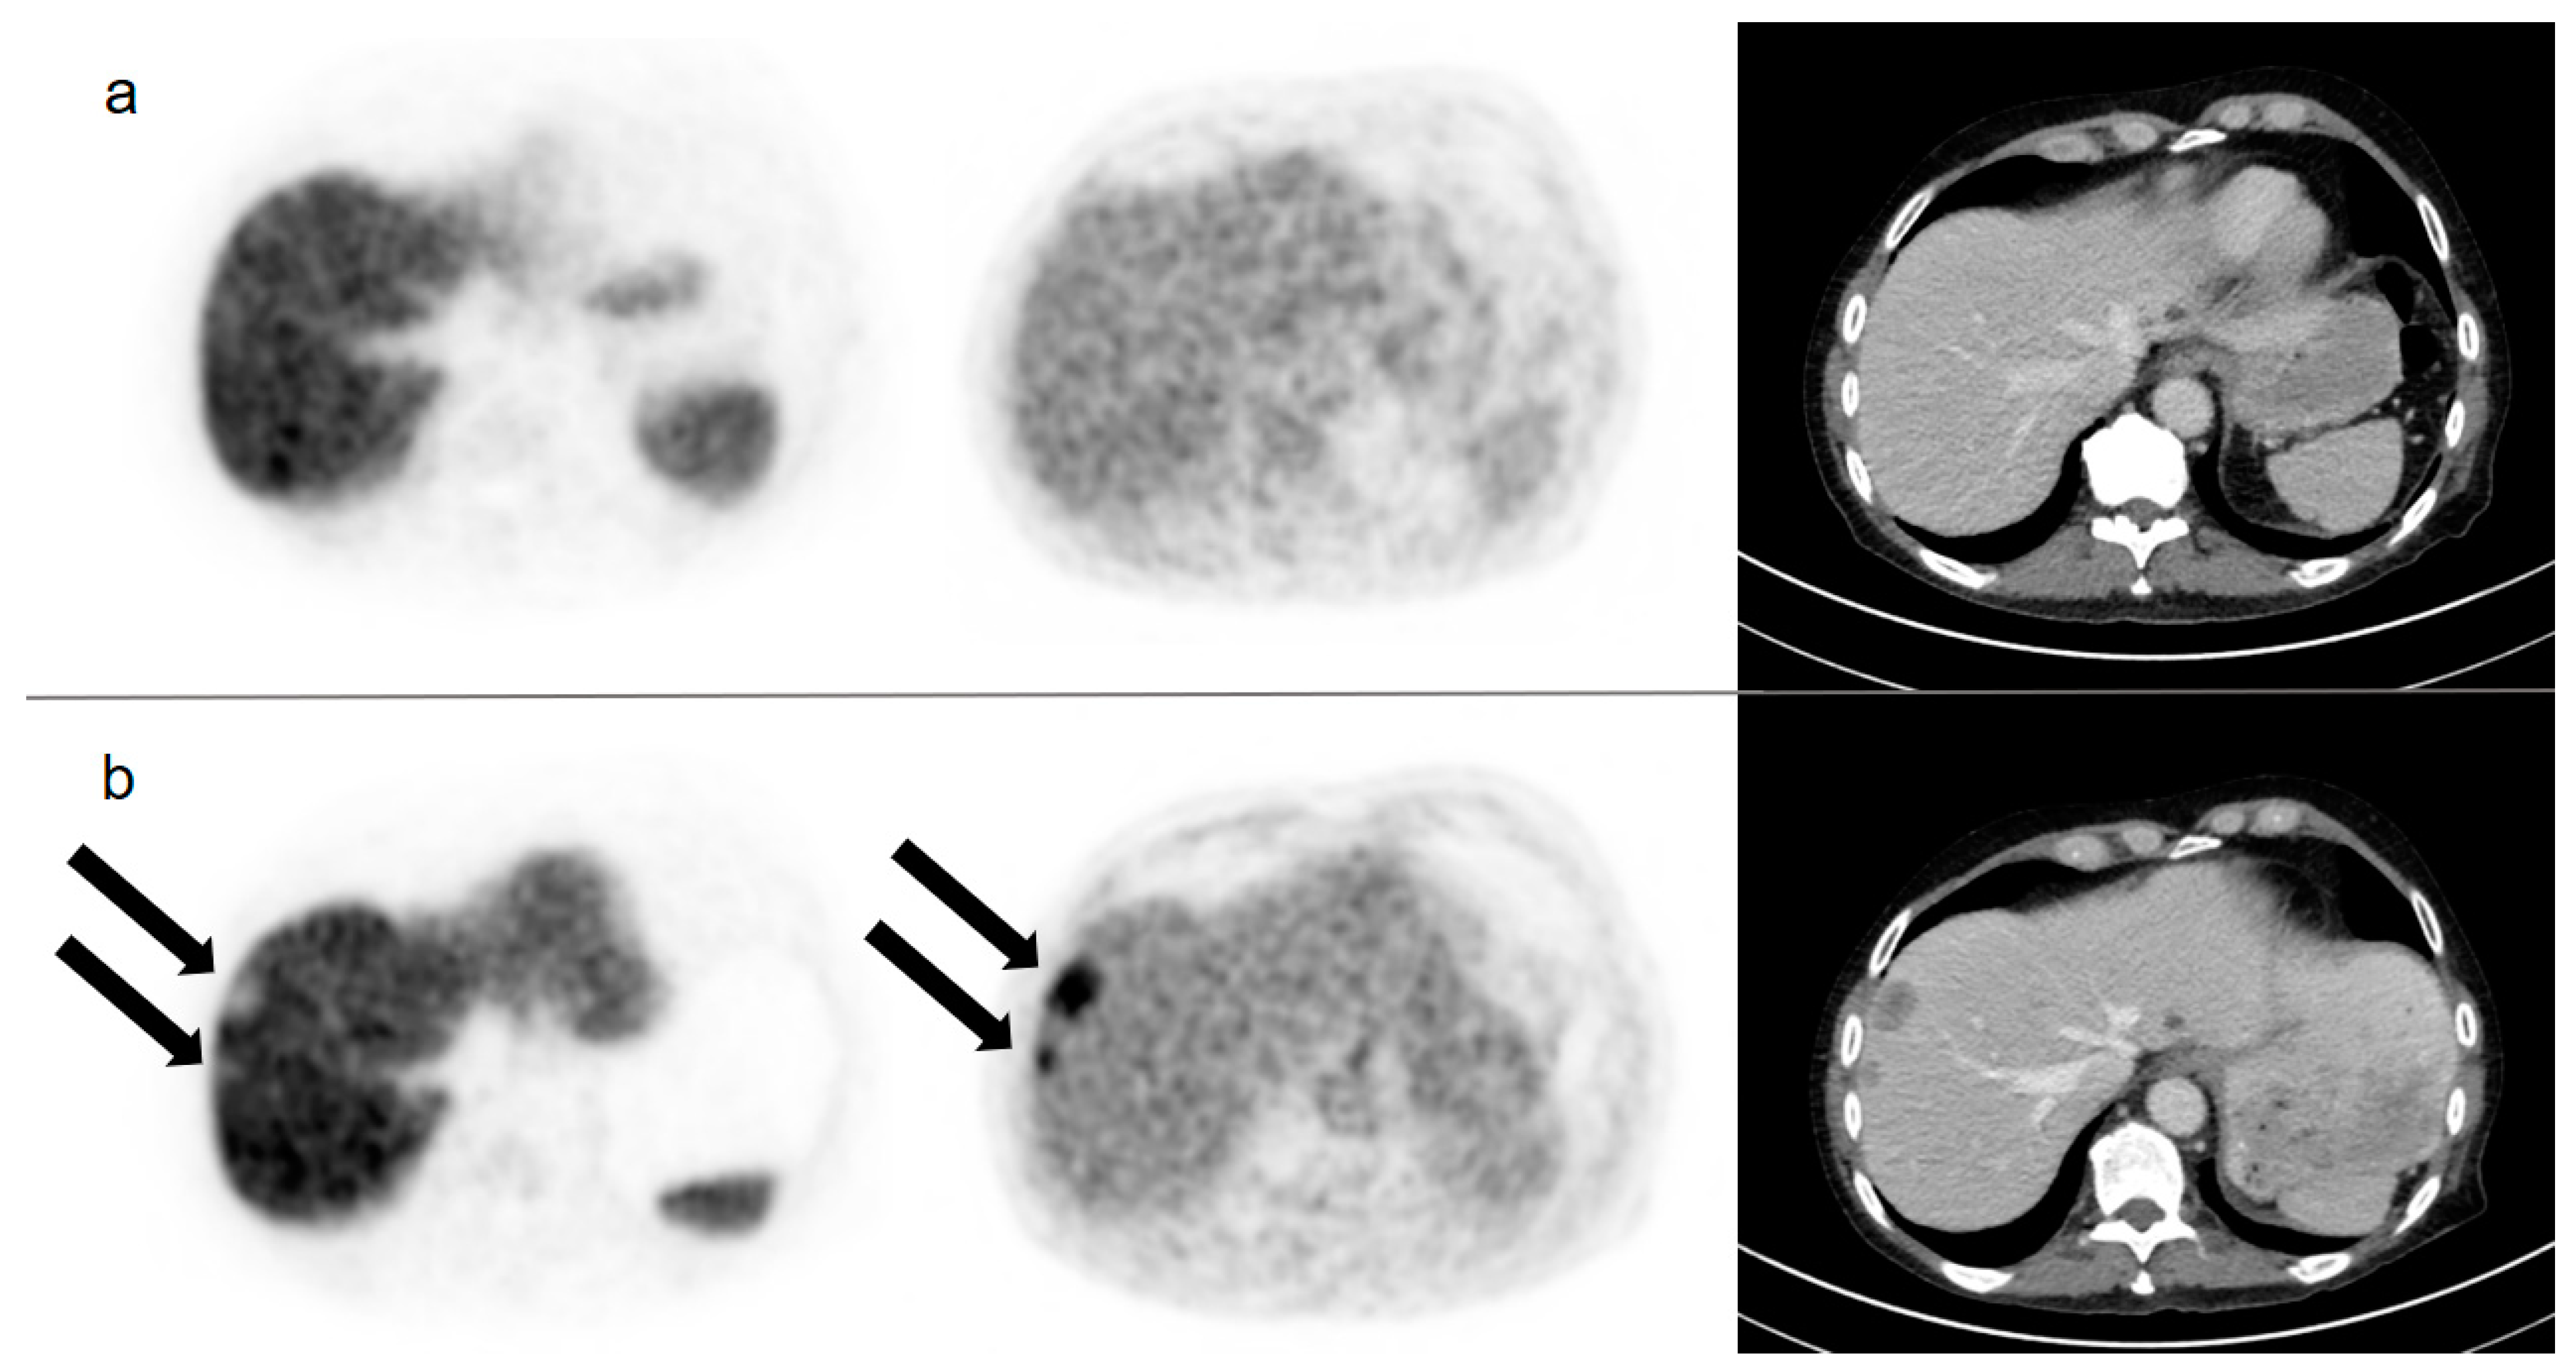

| 3 | >10 | DBMI | 1 | OSS | − | − | − |

| 4 | DBMI | DBMI | 2 | HEP * | − | − | − |

| 7 | >10 | >10 | n.a. | n.a. | >10 | 1 | OSS |

| 10 | >3 but <10 | >3 but <10 | 4 | HEP **, PeC | >10 | 7 | HEP **, PeC |

| 14 | >10 | >10 | n.a. | n.a. | >10 | 3 | HEP |

| 23 | >10 | >10 | 1 | LN | >10 | 9 | LN |